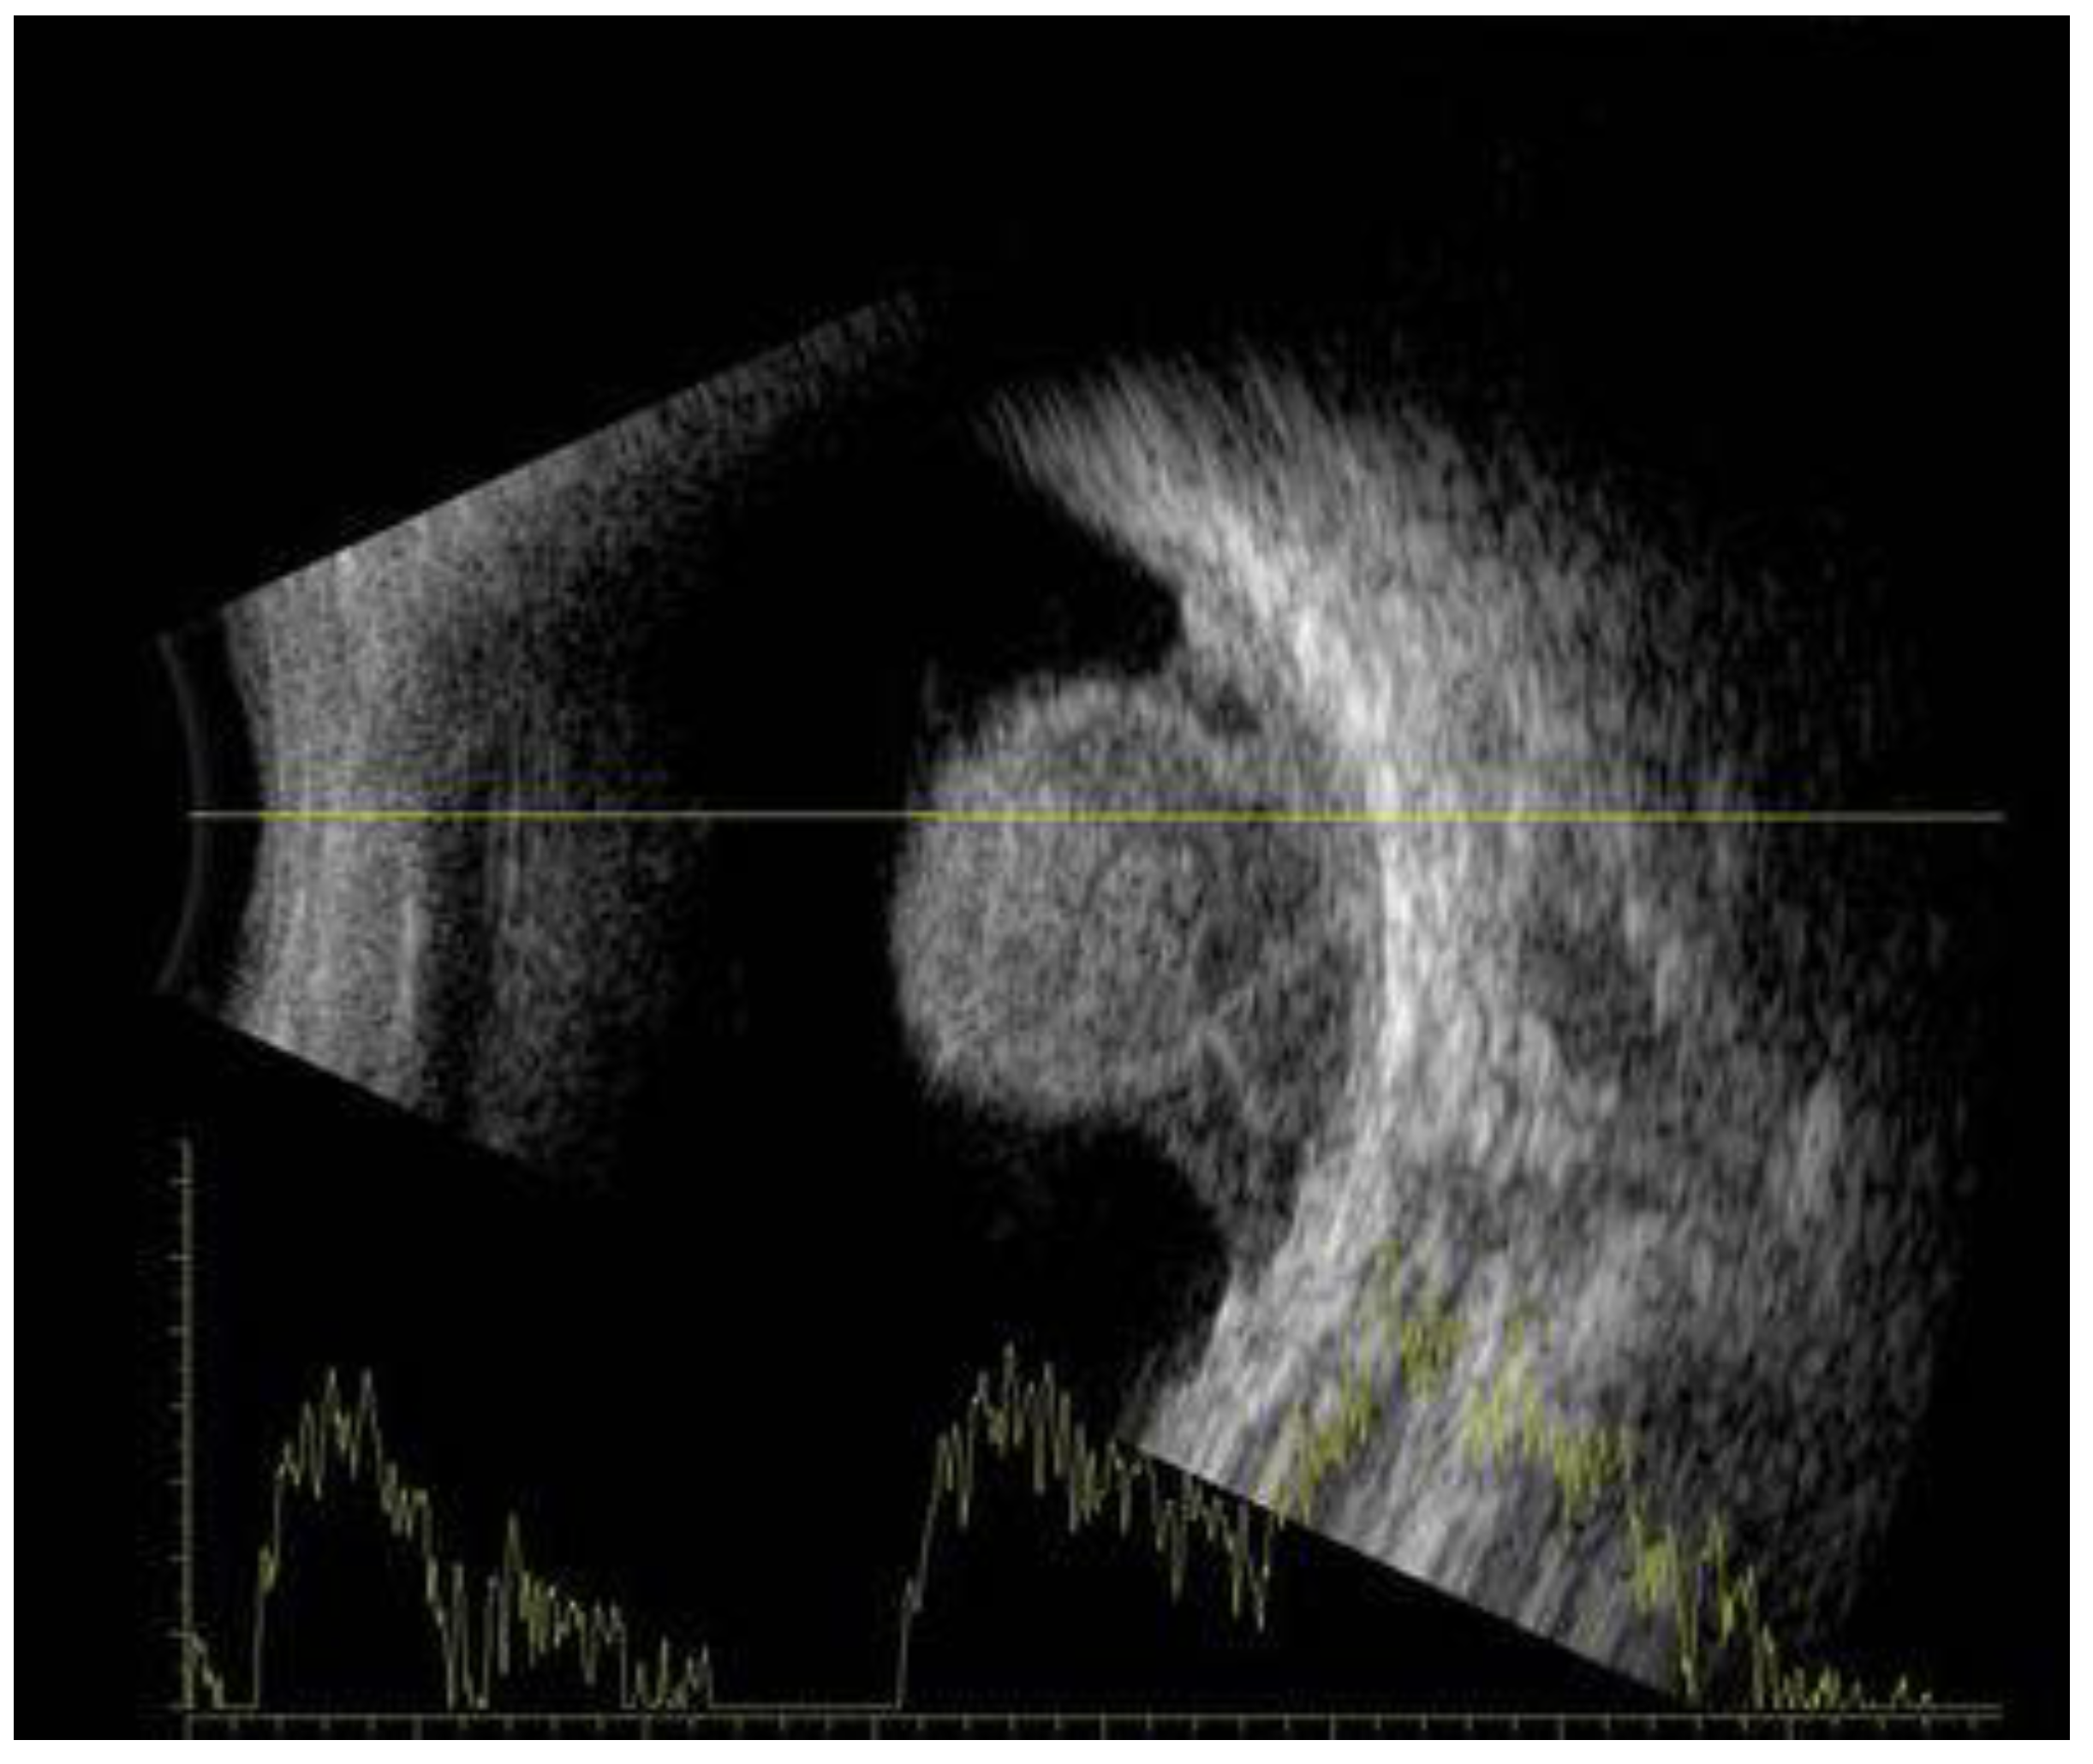

6. History

7. Physical Examination and Evaluation